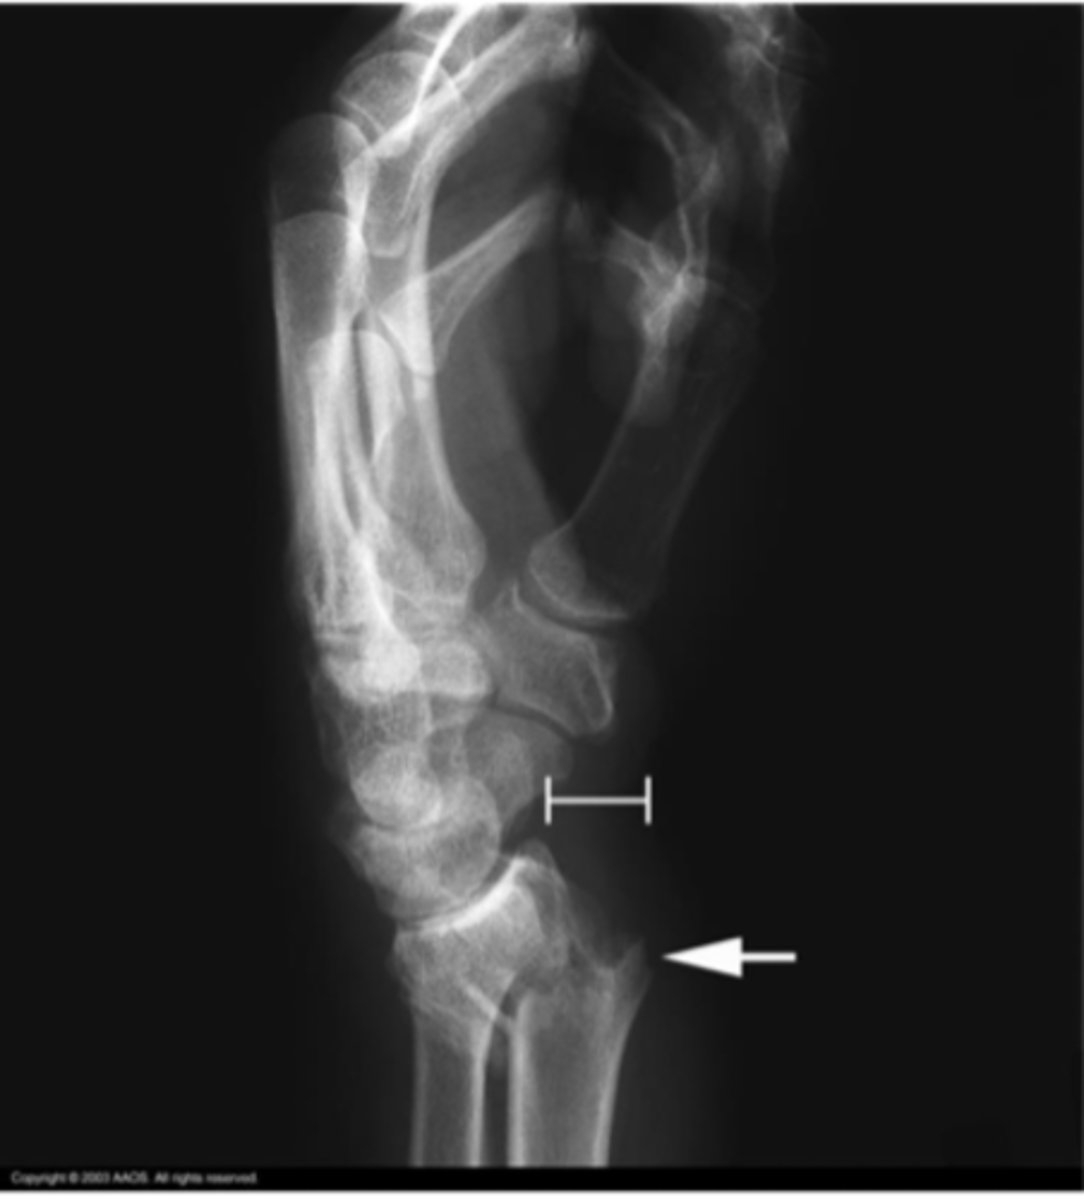

DISI

What is the issue?

Terry Thomas sign (DISI)